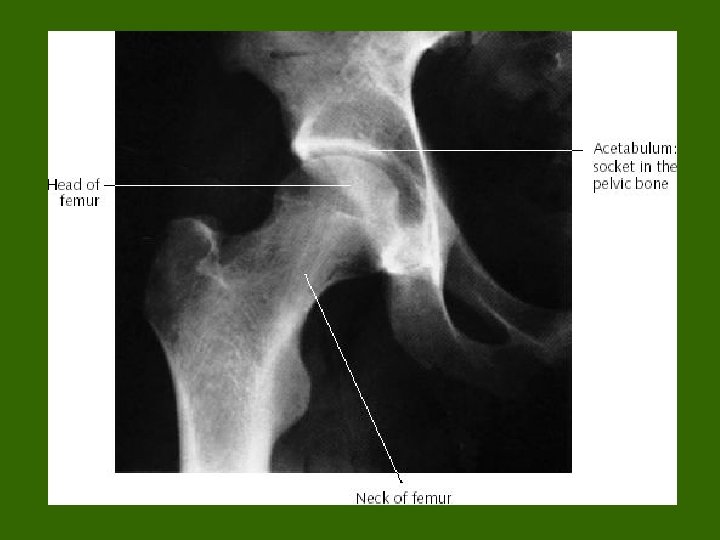

1. gornji okrajak (ekstremitas proksimalis) tzv“proksimalni femur“ Klinički značaj: -Glava femura (caput femoris) nosi zglobnu glačicu za zglob kuka (art. coxae) i spajase sa acetabulumom, zglbnom čašicom na karličnoj kosti (os coxae) -Glava femura nosi lig. capitis femoris (trofički ligament kroz koji prolazi krvni sud koji ishranjuje glavu i deo vrata femura). Ako se pokida , naročito kad starijih osoba , često je potrebno ugradidi veštački kuk (nekroza) -

Vrat femura (collum femoris) – česte frakture, naročito kod osteoporotičnih kostiju (menopauza, poremećaj metabolizma kalcijuma kod nekih endokrinih bolesti i sl. ) - Definisali smo geometrijski(matemtički) model vrata femura – klinički značajno zbog adekvatne pozicije šrafova kojima se pričvrščžćuju delovi vrata kod fraktura vrata - trohanteri (veliki i mali) – definisati tzv. “trohanterični region“ gornjeg okrajka (proksimalnog femura) - značaj tzv. kolodijafiznog ugla - značaj tzv. subcapitalnih fraktura - rentgen anatomija proksimalnog okrajka femura